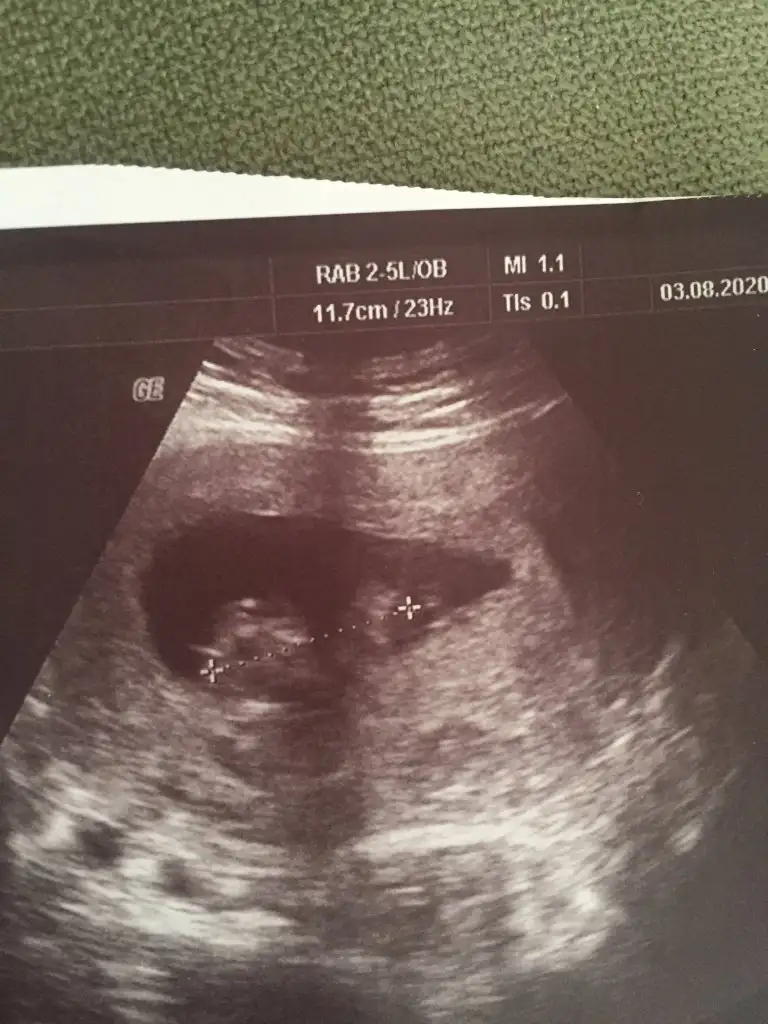

Merhaba kızlar 10+4 haftalık olduk bugün mecburen doktora gittim iki gündür kanlı ishal oldum hastane de serum taktılar kadın Doğua da gittim bebek iyi dedi doktor doktorum cinsiyetle ilgili hiç yorum yapmıyor nuba göre cinsiyet tahmini yapabilen arkadaşlar bi yardımcı olsanız

Resmî yükledim

Eklentiler

• 4D7B5CF4-01CE-47A6-93B1-B70F70CB9CA2.webp

4D7B5CF4-01CE-47A6-93B1-B70F70CB9CA2.webp

42,3 KB · Görüntüleme: 35